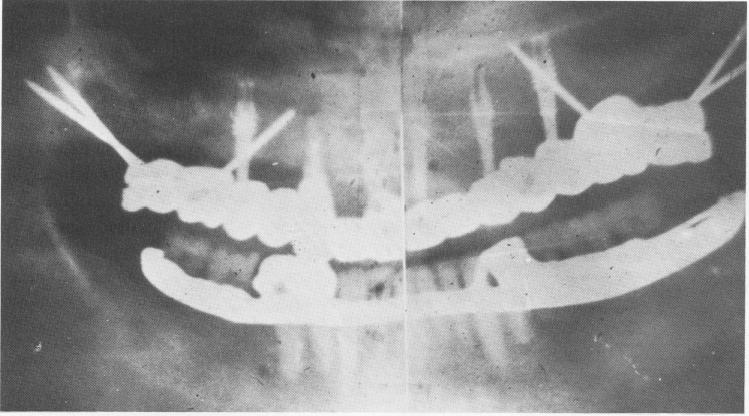

Fig. 10-187. A Panorex of the completed case showing the vent-plants and the tremendous spread of the tripodial pins, which were used to avoid the broad and low-flaring maxillary sinus.

2 Ventplants & spreaded tripodial pins avoiding maxillary sinus